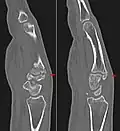

Carpal boss in CT.